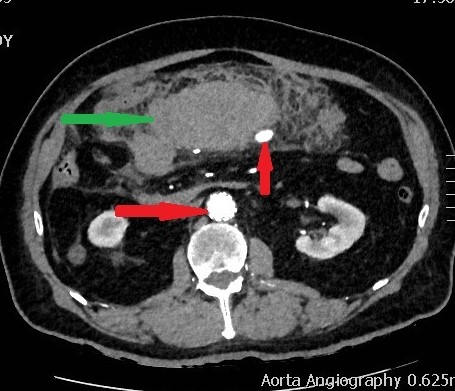

CT Αγγειογραφία. Πράσινο βέλος αιμάτωμα. Οριζόντιο κόκκινο βέλος stent στο AAA. Κατακόρυφο κόκκινο βέλος ψευδοανεύρυσμα τόξου Riolan (Ευγενική παραχώρηση Dr. V. Penopoulos)